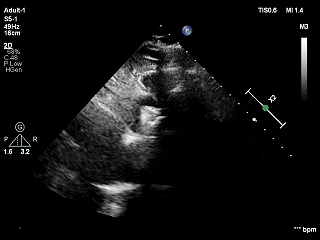

术前超声评估

经胸超声报告提示:患者二尖瓣2区及3区前叶关闭时脱入左房,二尖瓣重度反流(MR 4+),患者LA前后径约52mm,LVEDD约68mm,LVESD约42mm,EF值:65%,经胸超声测二尖瓣瓣口面积约6.1cm2,主动脉瓣无冠瓣脱垂并中重度反流,三尖瓣中度反流,估测中度肺动脉高压。

经胸短轴测得瓣口面积约6.1cm2

LVOT切面可见主瓣二尖瓣术后反流基本消失

植入两枚夹子后二尖瓣平均跨瓣压差2mmHg